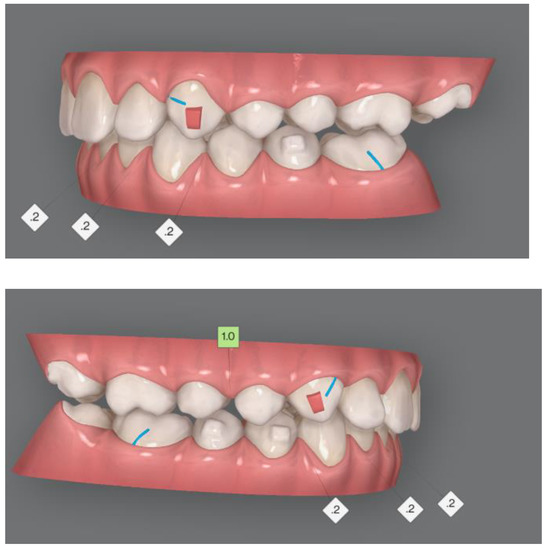

Figure 5. Aesthetic changes.

Post-treatment lateral teleradiograph showed a significant improvement in the sagittal bone relationship (Table 1), along with good vertical control, and a correct inclination of the upper and mandibular incisors. (Figure 4). A good proportion between the upper and mandibular arch width and shape was achieved along with a flat curve of Spee. Functional and aesthetic outcomes were stable at one-year follow-up and four-year follow-up (Figure 4, Figure 5 and Figure 6).

Figure 6.

Cephalometric changes.